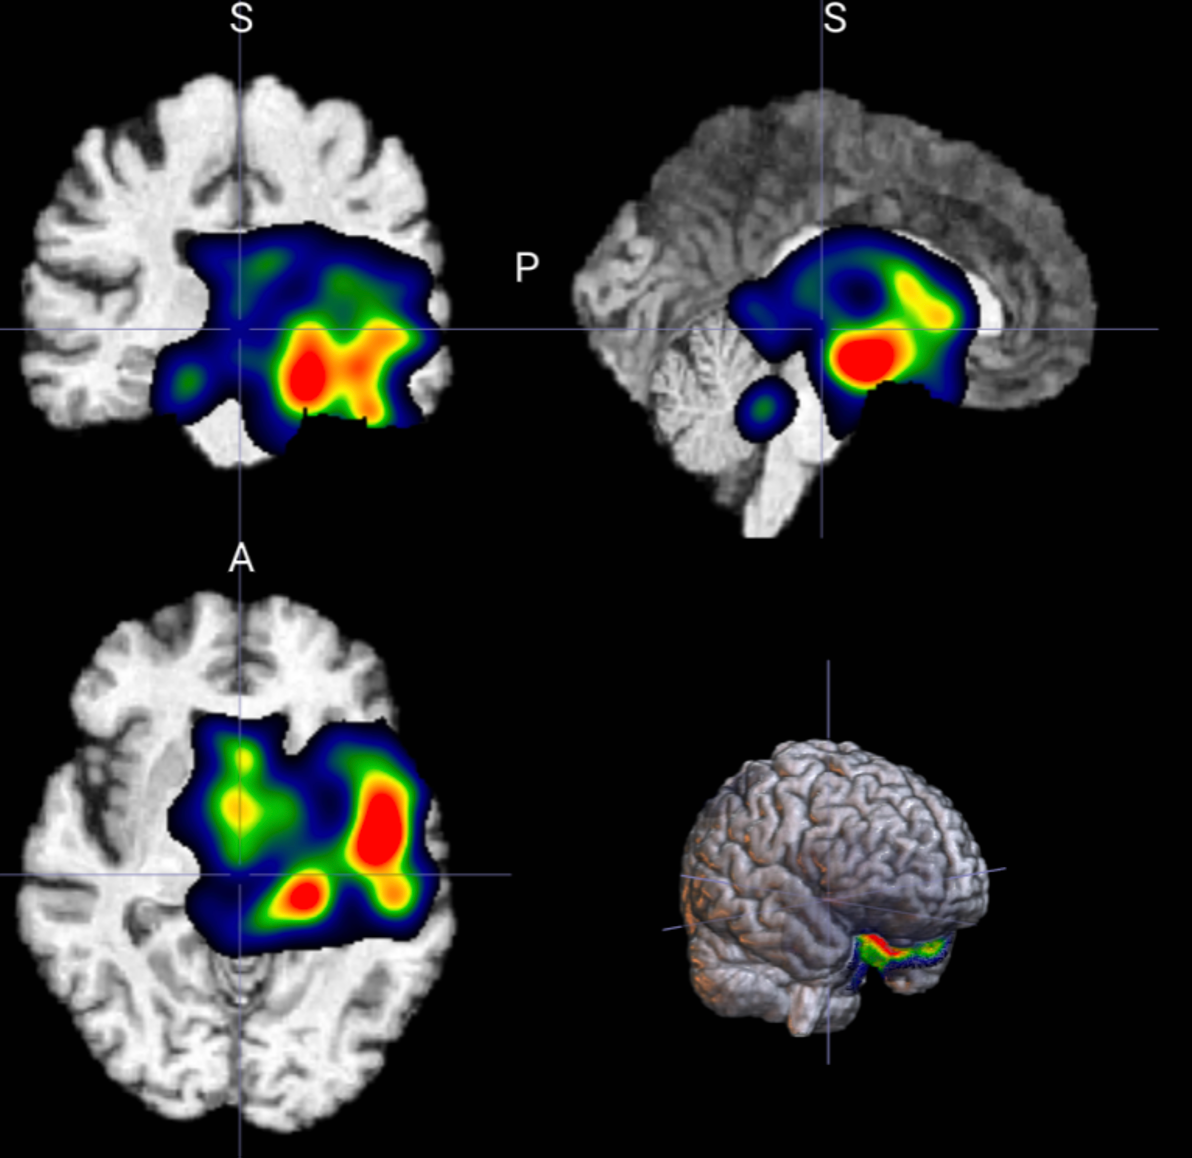

🧠 3D 图像分类模型SmoothGrad热力图生成

对3D图片生成基于 SmoothGrad 的注意力热力图(heatmap),用于模型可解释性分析。

3D可视化热图SmoothGrad